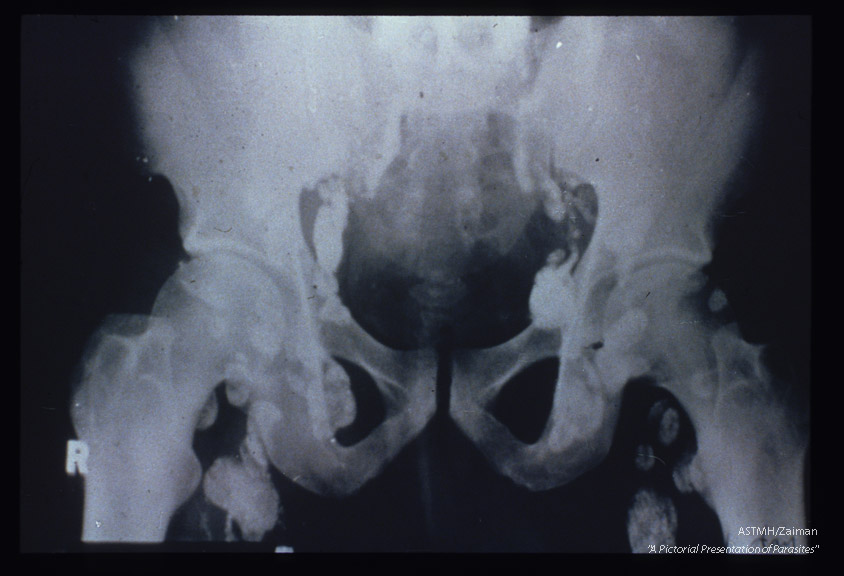

Lymphadenopathy demonstrated by x-ray.

Wuchereria bancrofti

Description: Lymphadenopathy demonstrated by x-ray.